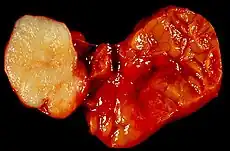

Salivary gland tumours, also known as mucous gland adenomas[1] or neoplasms, are tumours that form in the tissues of salivary glands. The salivary glands are classified as major or minor. The major salivary glands consist of the parotid, submandibular, and sublingual glands. The minor salivary glands consist of 800 to 1000 small mucus-secreting glands located throughout the lining of the oral cavity.[2] Patients with these types of tumours may be asymptomatic.[1]

Little is known about the total incidence of salivary gland tumours as most benign tumours go unrecorded in national cancer registries.[3] The majority of salivary tumours are benign (65-70%).[4] Within the parotid gland 75 - 80% of tumours are benign. Around 50% of the tumours found in the submandibular glands are benign. Sublingual gland tumours are very rare but if present, they are most likely to be malignant.[4][19] Saku et al. in 1997 [20] and Venturi [21][22] in 2021, reported the causal role for ionizing radiation in salivary gland tumorigenesis, particularly for mucoepidermoid carcinoma.